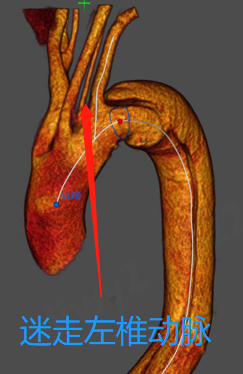

1、患者为Stanford B型胸主动脉夹层,迷走左椎动脉;

2、根据CTA平扫显示,患者为迷走左椎动脉,左椎动脉始发于左颈总动脉(LCCA)与LSA之间;

迷走左椎动脉

3、为获得充足的近端锚定区,选择将支架近端锚定在LCCA后缘。由于患者为右椎优势供血,故遮盖迷走左椎动脉并重建LSA;